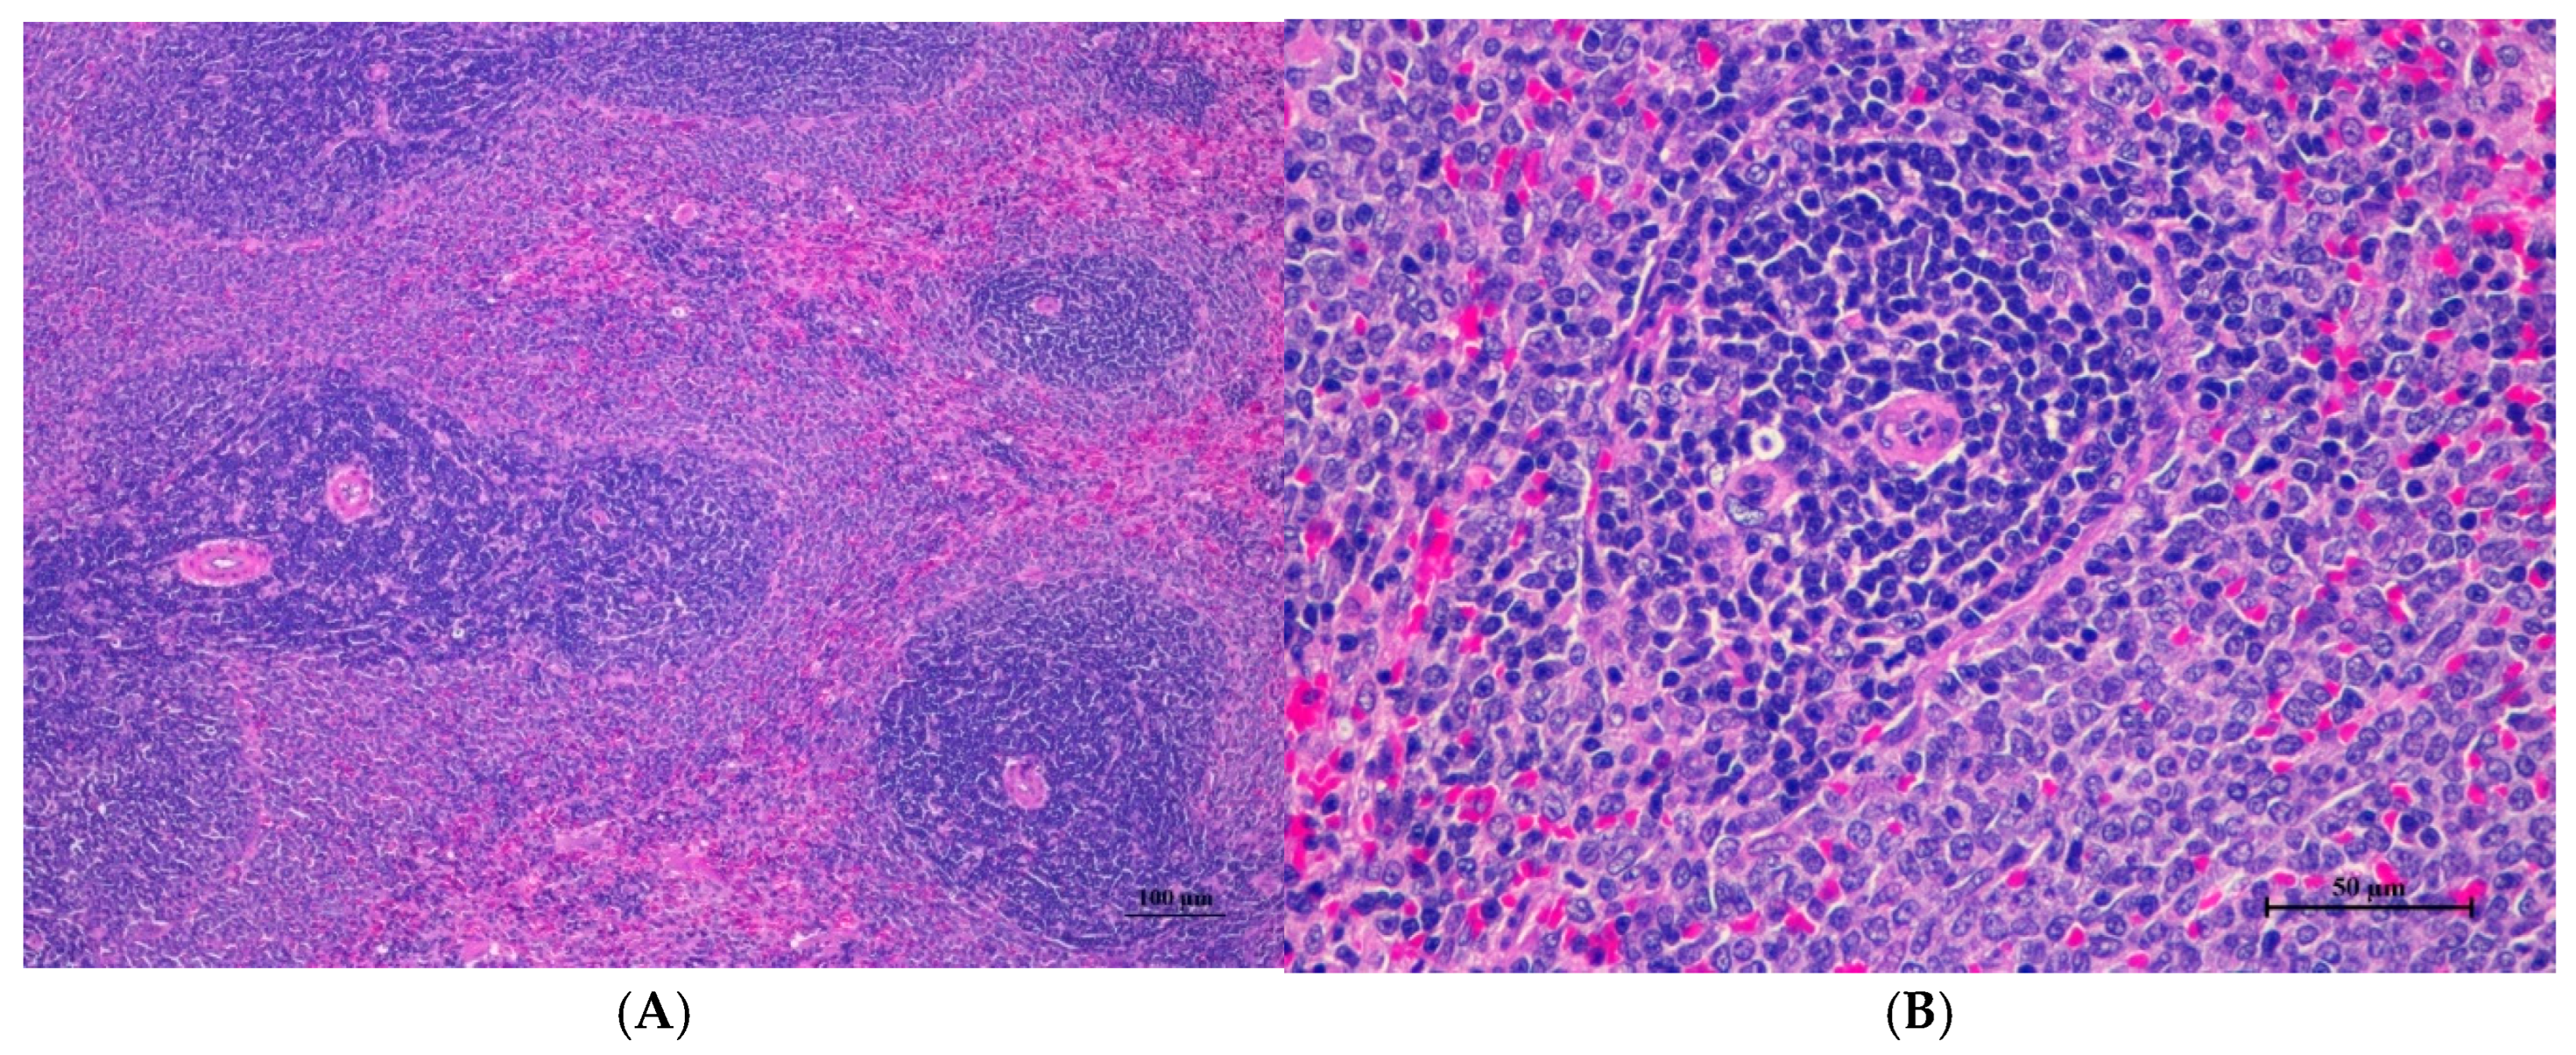

Figure 4.

Histopathological examination of rat splenic tissue in acute toxicity from single oral dose of CDF displayed normal microscopic structure. (A) Splenic tissue showed intact structure with distinct white pulp and red pulp regions (100×, H&E). (B) High magnification reveals normal lymphoid follicles with intact germinal centers. No histopathological abnormalities were observed (400×, H&E).

Histopathological analysis revealed generally unremarkable findings in the liver, kidney, heart, and spleen, with only minor, scattered hepatocellular swelling and vacuolation in the liver, mild renal tubular degeneration in limited kidney areas, and focal myocardial vacuolation and lymphoid aggregation in the heart. Conversely, the lung exhibited significant pathological changes, characterized by alveolar septal thickening due to severe interstitial infiltration of lymphocytes and other mononuclear cells, nodular lymphoid aggregations, alveolar septal engorgement and hyperemia, alveolar edema, and multifocal mild alveolar hemorrhage, suggesting a potential site of inflammatory response.